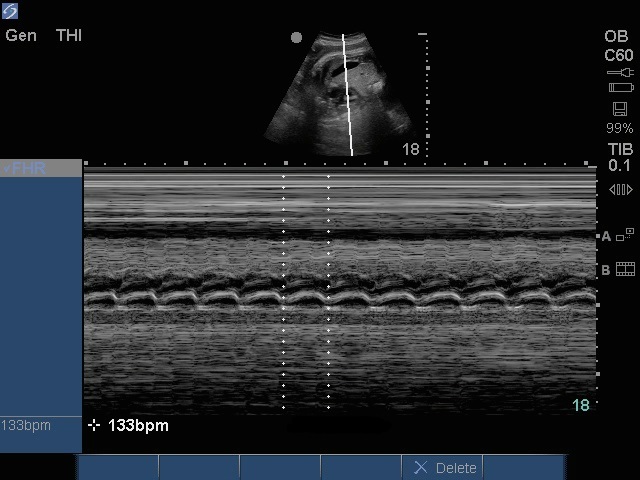

盆腔胎儿心脏图像